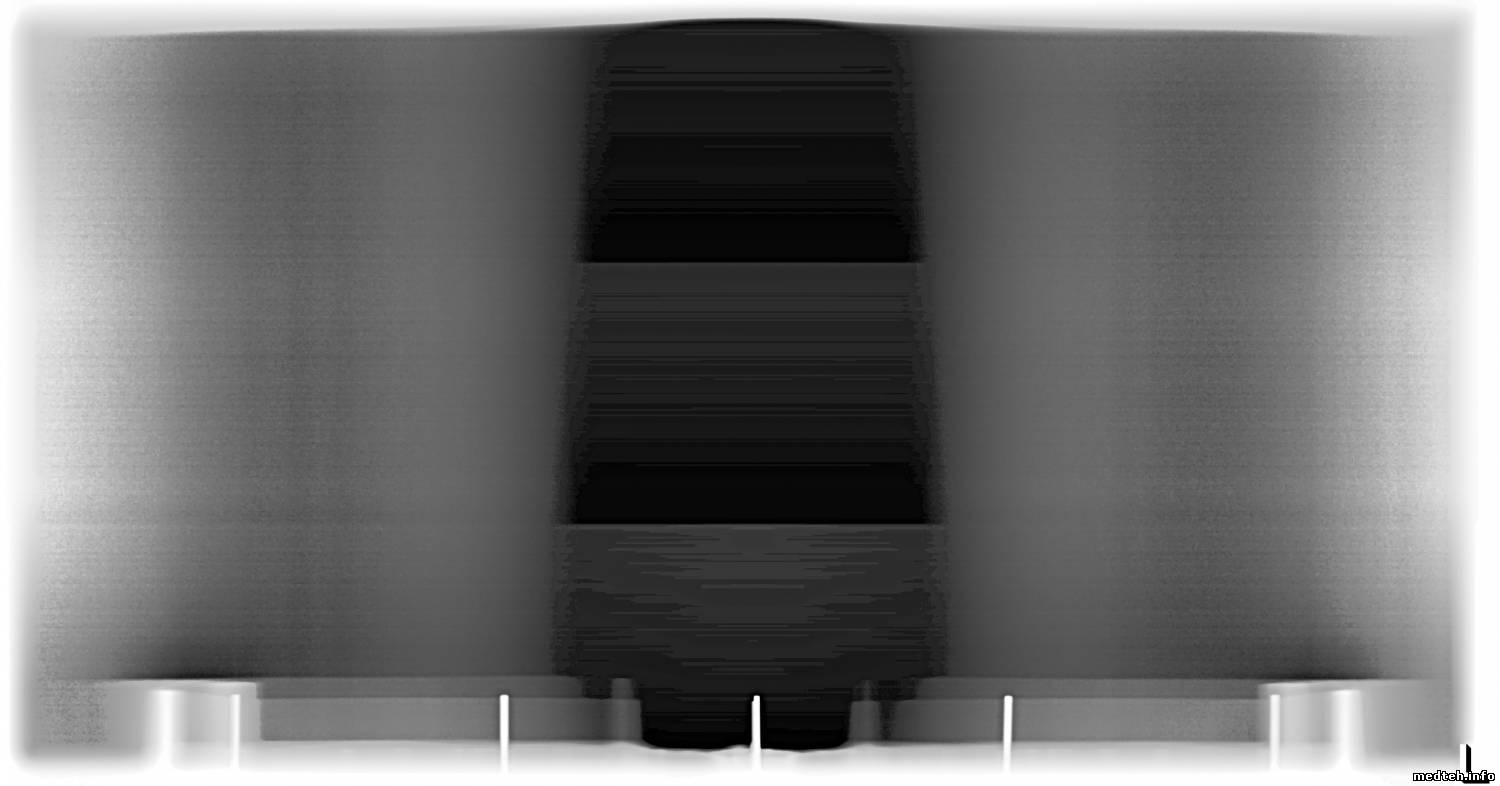

Геометрические искажения, там калибруються тоже программно, а вот горизонтальные полосы на снимке, ума не приложу, как убрать. Несколько снимков во вложении. На середине снимка хорошо видно 3-и приёмника (детектора). Чем дальше,тем хуже. Чётче видны горизонтальные полосы.